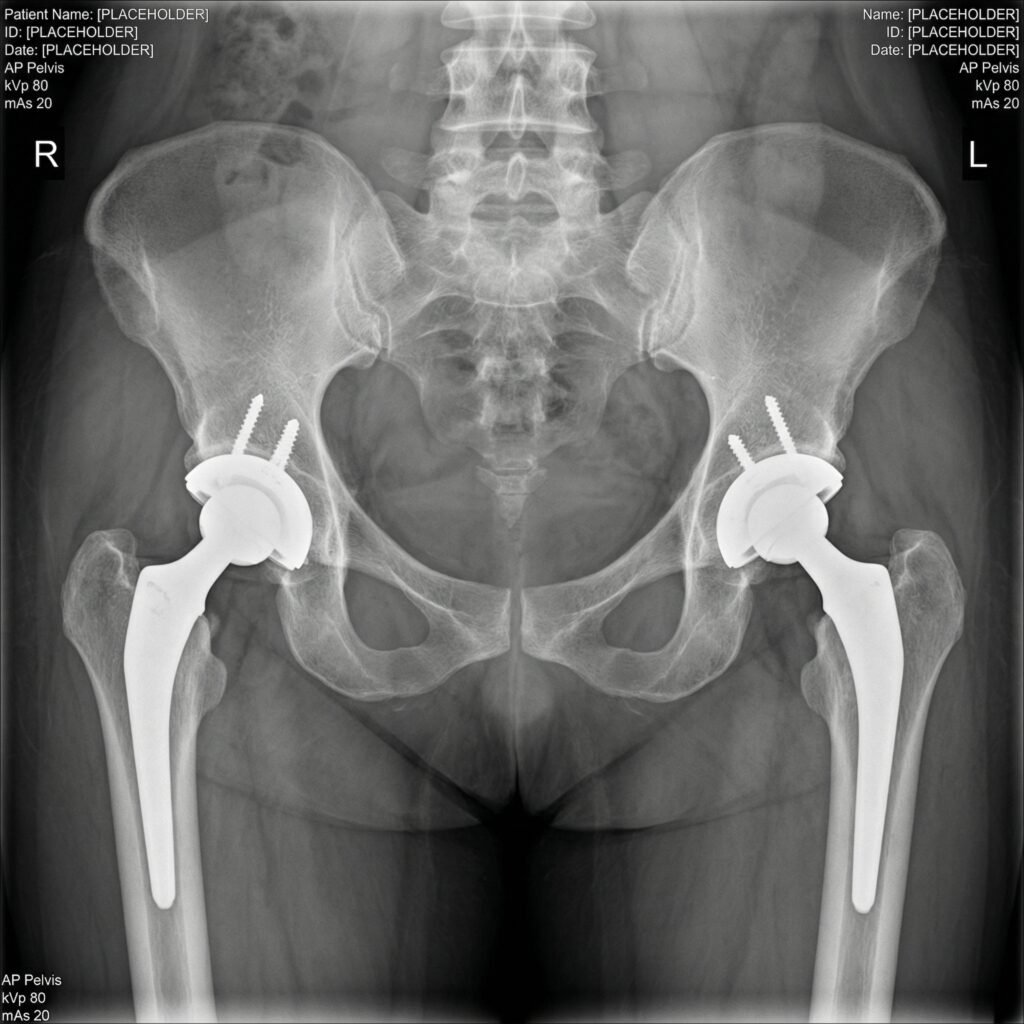

During the procedure, the damaged hip joint is replaced with a high-quality artificial implant designed to replicate natural movement. Depending on the patient’s condition, either total or partial hip replacement may be recommended after a detailed clinical evaluation.

At Dr. Shreyansh Shukla’s clinic, every patient undergoes thorough assessment including medical history, physical examination, and imaging such as X-rays to determine the most appropriate surgical approach. With the use of modern techniques and precision-based care, the procedure ensures reduced pain, improved joint stability, and faster recovery.